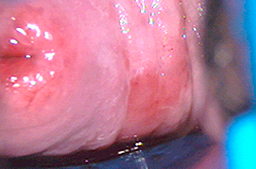

La Crioterapia o Criocirugía ha sido utilizada para destrucción de la piel con lesiones del Virus del papiloma humano. Tiene el mismo inconveniente que los aparatos de electrocirugía ya que no mide la profundidad adecuadamente. La tasa de éxito inicial es del 83% con una recurrencia del 28% los primeros dos años. Debido al daño de las terminaciones nerviosas puede ocasionar, hipersensibilidad en los genitales.